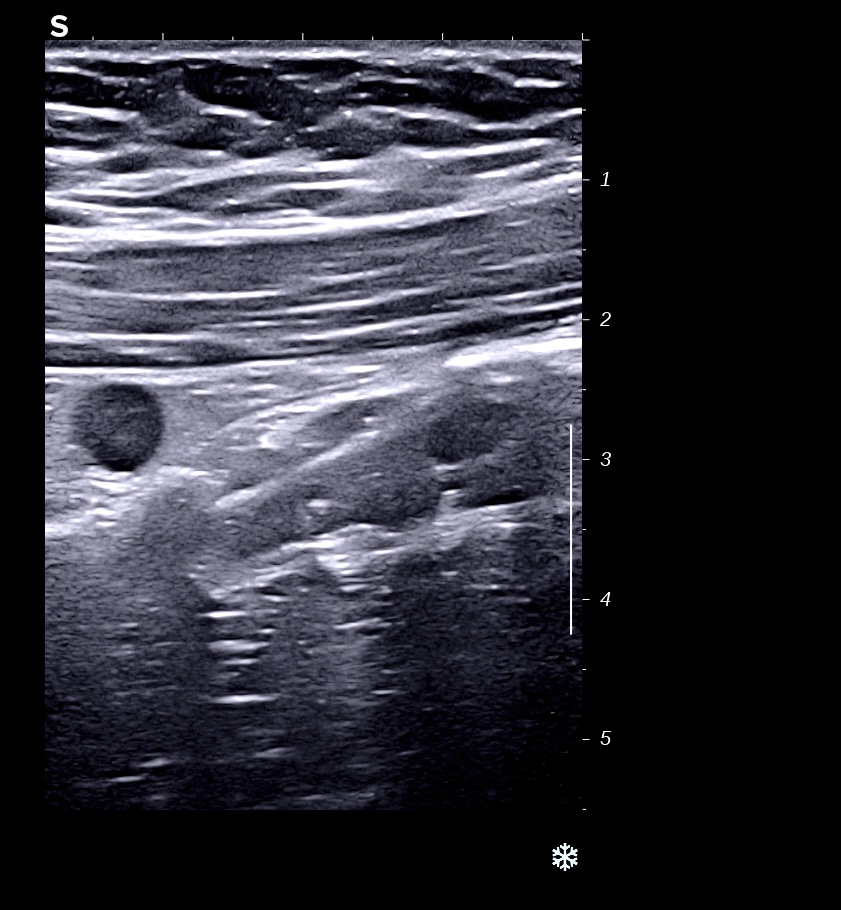

RCH classique, respect de la structure en couche,sous muqueuse très épaissie; musculeuse intacte

Classiquement dans la RCH, l'épaississement concerne les couches 2 et 3, c'est à dire muqueuse (hypoéchogène) et sous muqueuse (hyperéchogène) car il s'agit d'une maladie superficielle de la paroi, la musculeuse (4 ième couche hypoéchogène) est intacte et donc le bord externe est linéaire et régulier

L'épaississement prédomine à la 3 ième couche hyperéchogène (qui fait > 1/3 de la paroi)

Perte des haustrations (le bord externe du colon est rectiligne, lors de la cicatrisation on retrouve des haustrations)

Épaississement continue, circonférentiel, symétrique.

L'épaississement prédomine à la 3 ième couche hyperéchogène( > 1/3 de la paroi), il est continue, régulier, cironférentiel

La structure en couche est conservée